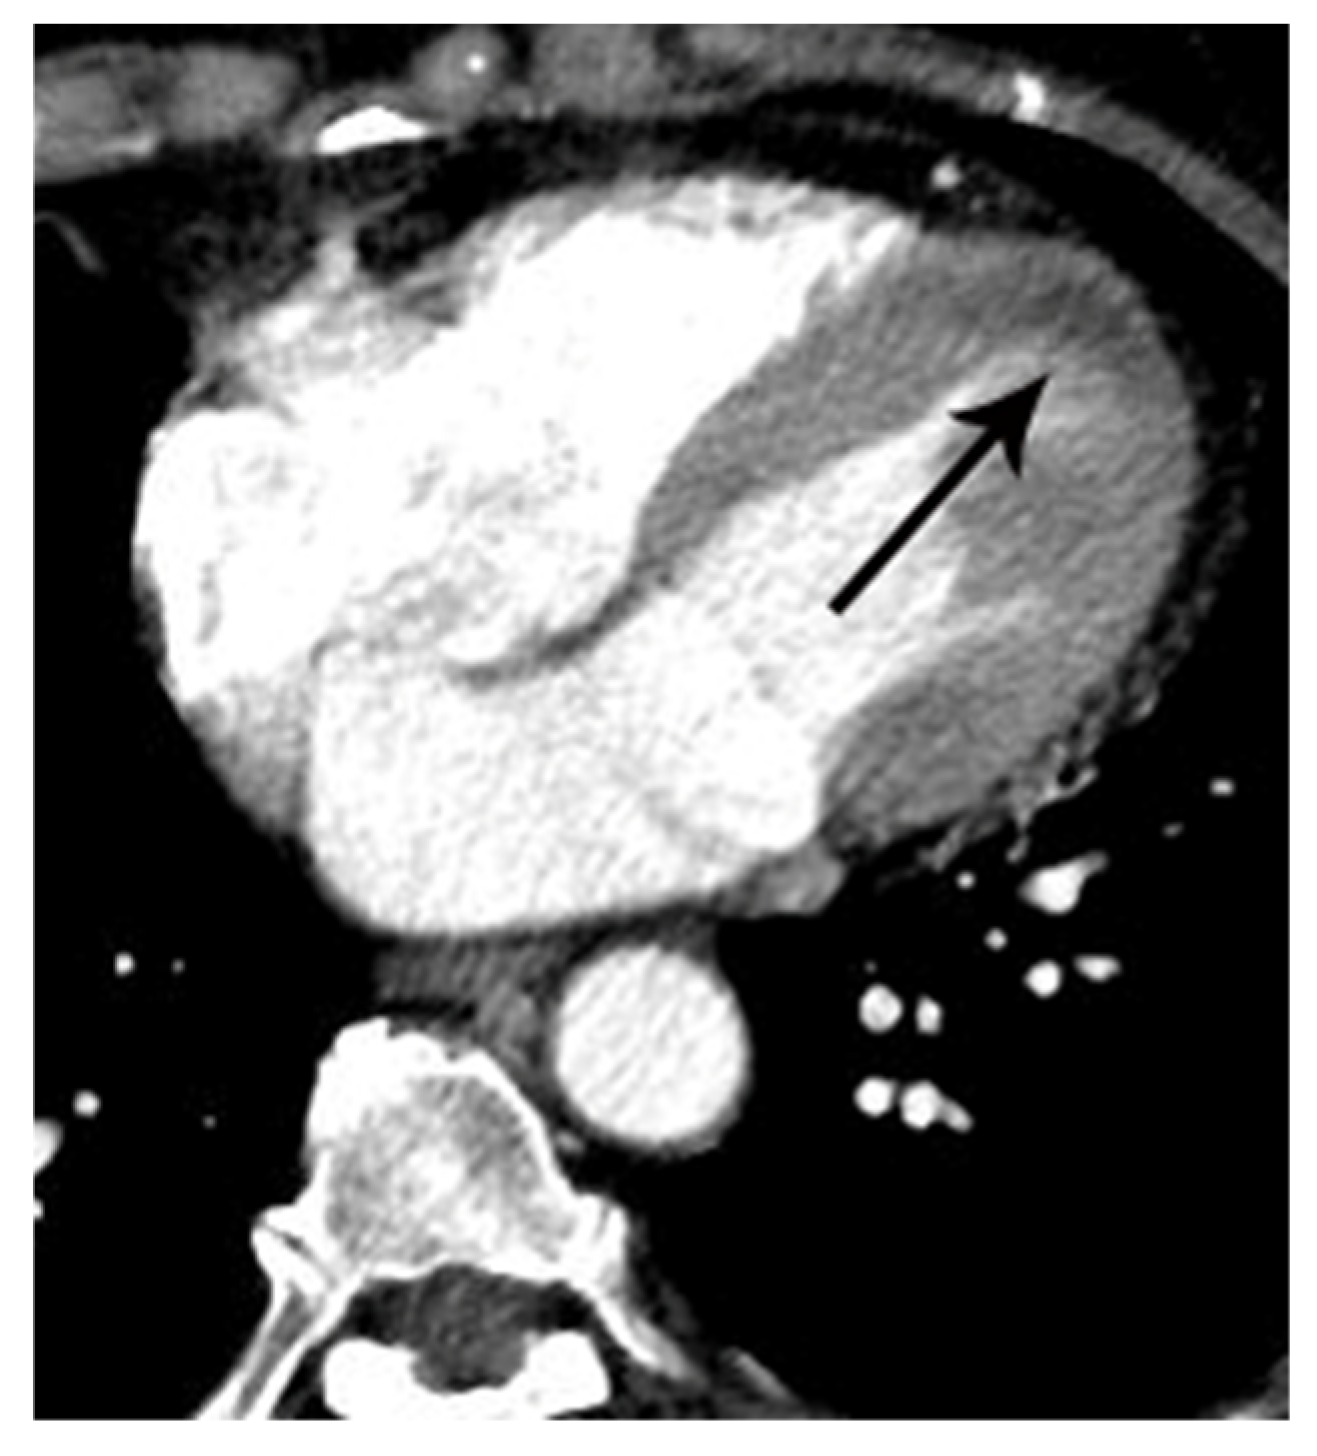

Figure 5.

False positive myocardial perfusion defect (MPD) in a 55-year-old female with acute chest pain. Focal low attenuation (arrow) in the left ventricular apex was noted on an axial CT image. The lesion was given a CT score of 2 for MPD. However, serial ECG and serum cardiac troponin were normal, and her final diagnosis was reflux esophagitis.